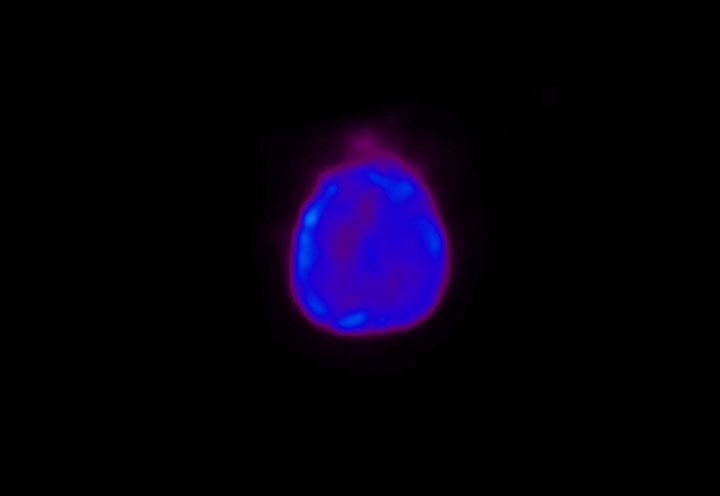

Head / Case4 : Amyloid

Sagittal

Courtesy : Kindai University Hospital

- Imaging protocol

- Injected dose: 3.21 MBq/kg, 18F-Flutemetamol

- Uptake time: 100 minutes

- Scan time: 20 minutes